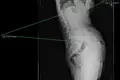

COMPORTAMENTO Levados ao limite, os distúrbios alimentares matam. Tratados, são curáveis. No verão, as adolescentes expõem os corpos, comparam formas, tomam decisões. Algumas escolhem o caminho da privação alimentar. Desde 2010 realizaram-se 12.858 consultas e só em 2015 foram 47 os internamentos no Hospital de Santa Maria. Patrícia é um caso-limite. Há 25 anos sofre de anorexia nervosa. A doença provocou-lhe uma severa osteoporose e, quando estava a morrer, apenas nos Estados Unidos encontrou solução para lhe sustentar a coluna. Conta o que passou para que não se repita